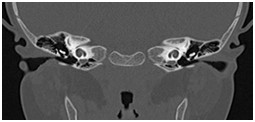

影像科在五官疾病诊治中的严谨、专业,全面开展眼、耳、鼻、喉精细化检查及诊断。

颞骨及耳(病例-前庭导水管扩大)